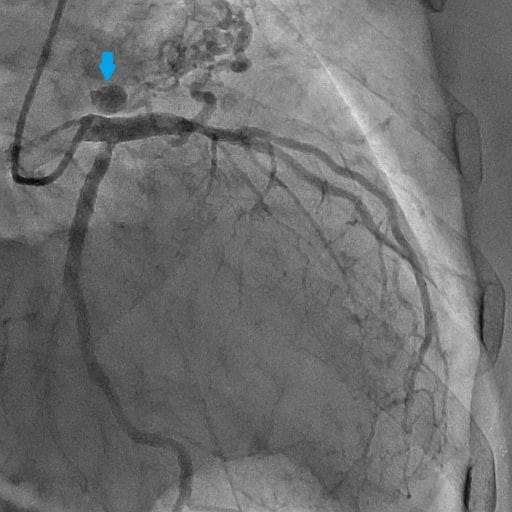

図4.冠動脈造影(左冠動脈)LAO:CRA

左冠動脈造影にて瘤を伴った左冠動脈肺動脈瘻を認める。

図5.冠動脈造影(右冠動脈)AP拡張期

右冠動脈造影にて右冠動脈肺動脈瘻を認める。